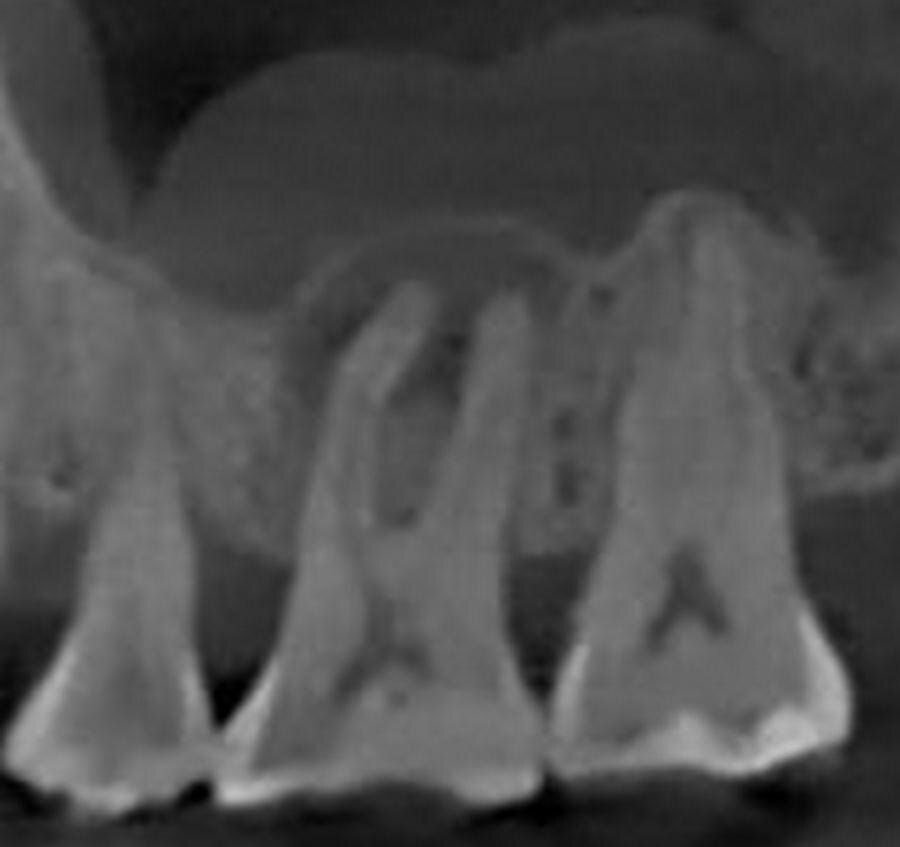

Зуб до лечения

Радикулярная киста зуба 1.6

Зуб Яны отреагировал иначе. Пульпа начала отмирать, но болезненных ощущений не было, или пациентка не обратила на них внимания из-за аллергии и ортодонтического лечения🤕 В результате длительного воспаления без лечения образовалась киста. К сожалению, заметить воспаление можно было только на КТ или рентгене. Внешне зуб был полностью здоров, пломба плотно прилегала, не было признаков воспаления или вторичного кариеса.